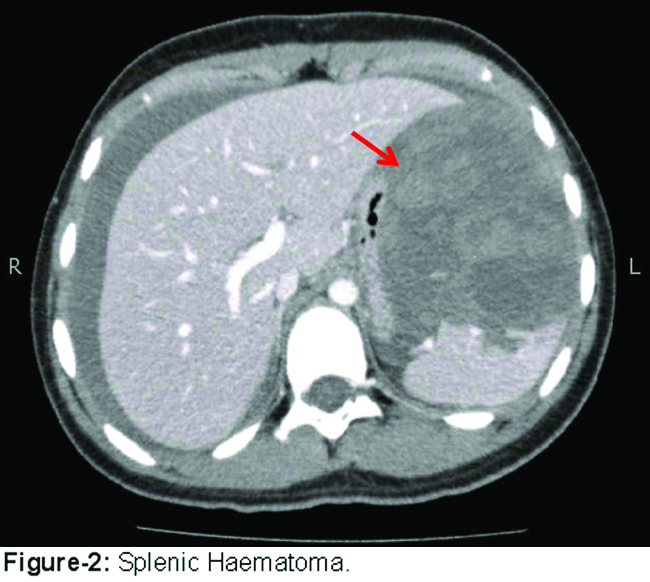

Approximately 3 months later, she presented again to ED with abdominal pain. Her repeat haematosis workup, including FXIII screen, was again normal. An urgent CT scan revealed a large splenic haematoma measuring 10.5 x 8.0 cm associated with complete laceration of the spleen (Figure-2).

Splenic angiogram was done to rule out any vascular abnormality. It was unremarkable. She was managed conservatively with packed cell and FFP transfusion. Her rheumatologic work-up (ANA, dsDNA, ASMA, AMA, anticardiolipin and antiphospholipid antibodies) was also unremarkable.